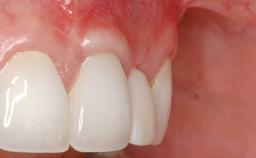

A 30-year-old woman was referred by her general dentist for evaluation of an esthetic complication related to previous implant treatment for congenitally missing maxillary lateral incisors. The patient’s chief complaint was the inadequate esthetic appearance of her smile. The case demonstrates the use of a combined approach to achieve optimal results. Two different flap designs - a tunnel technique and a coronally advanced flap - are employed based on the surgical objectives for the affected site.

Soft Tissue Anatomy Intact Defective

Soft Tissue Contour and Volume Slightly compromised